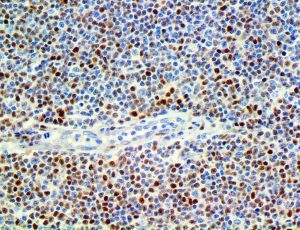

The first cytokines released are interleukin 1β (IL-1β) and tumor necrosis factor-α (TNF-α), which attract a variety of circulating white blood cells (WBCs) to the infection site, including neutrophils, monocytes, macrophages, and natural killer (NK) cells. This response, along with the antipathogenic chemicals released by these cells (i.e., complement), comprise the innate immune response. These cells directly attack the invading pathogen and also release additional cytokines, chief among them interleukin-1 and 6 (IL-6). IL-6 is essential for invoking the adaptive immune response, which calls T-cells, B-cells, and T helper (Th) cells to the infection site. IL-6 also stimulates further recruitment, proliferation and activation of macrophages.

It is the ICU physician who is most likely to witness one of the deadliest manifestations of the abnormal immunological response, the cytokine storm syndrome (CSS). This response is also referred to by some as the cytokine release syndrome (CRS). CSS is characterized by continuous activation and expansion of macrophage and lymphocyte populations, which secrete large amounts of cytokines, causing the cytokine storm. This massive cytokine release is akin to hemophagocytic lymphohistiocytosis (HLH) disease, a syndrome characterized by initial unchecked and persistent activation of cytotoxic T lymphocytes and NK cells.